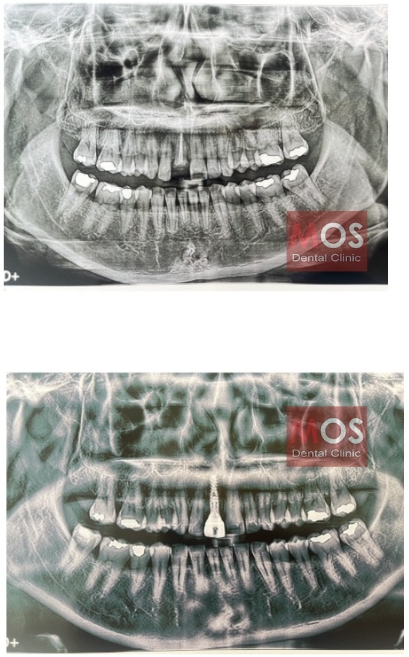

ตัวอย่างเคส

เคสคนไข้รากเทียม 1

เคสคนไข้รากเทียม 2

เคสคนไข้รากเทียม 3